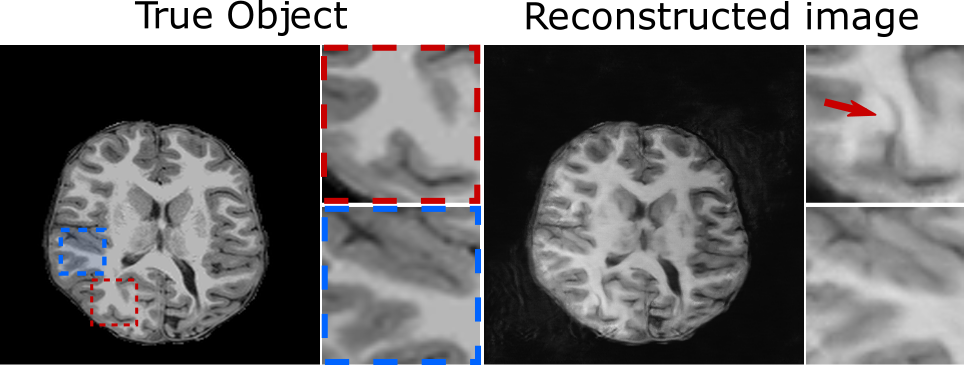

Figure showing two common types of tomographic hallucinations introduced through image reconstructionA schematic of hallucinations from DL-based reconstruction of a clinical pediatric MR brain image with training performed on adult brain images. The artifact outlined in red shows a realistic fold-like structure that has been hallucinated by the DL-based method, while the artifacts outlined in blue are from separate sources of scanner error.

Kelkar, Bhadra, and colleagues provide a formal definition of hallucinations based on fundamental principles of imaging science. Through numerical studies, they evaluated the presence and impact of hallucinations across both DL-based and non-data-driven reconstruction methods. These methods were used to reconstruct images of adult and pediatric brain tissue — with the DL-based method trained only on adult brain images — and evaluate the effect of bias from the training images.

“A hallucination could be something minor, such as a slight imperfection at the boundary of a tissue, or it could be something major, like introducing an entire fold of tissue in the brain,” Kelkar said.